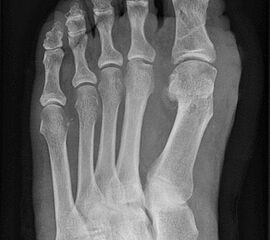

Abbildung 27

Dislokation des MTK 1 bei zu starker Verschiebung oder/und unzureichender Osteosynthese. Am häufigsten scheint die laterale Verkippung des MTK 1 aufzutreten 19146. Abbildung 27 zeigt eine solche Komplikation am 2. postoperativen Tag. Es folgte die sofortige Revision, mit Schluss der Osteotomie, Austausch der Schraube und Rotationssicherung über einen zusätzlichen Draht.